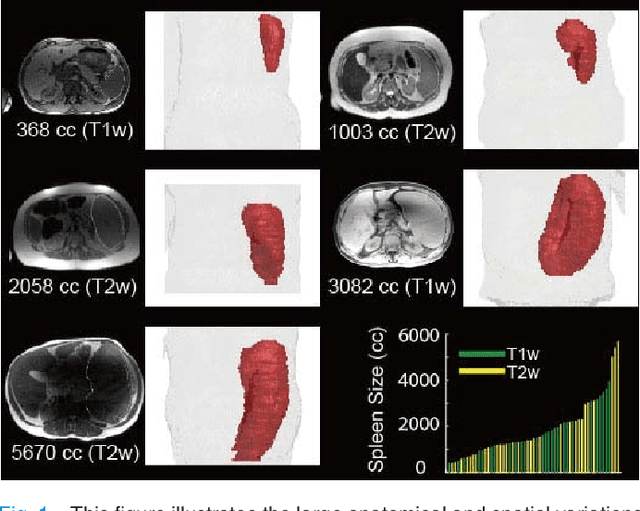

Abstract:The findings of splenomegaly, abnormal enlargement of the spleen, is a non-invasive clinical biomarker for liver and spleen disease. Automated segmentation methods are essential to efficiently quantify splenomegaly from clinically acquired abdominal magnetic resonance imaging (MRI) scans. However, the task is challenging due to (1) large anatomical and spatial variations of splenomegaly, (2) large inter- and intra-scan intensity variations on multi-modal MRI, and (3) limited numbers of labeled splenomegaly scans. In this paper, we propose the Splenomegaly Segmentation Network (SS-Net) to introduce the deep convolutional neural network (DCNN) approaches in multi-modal MRI splenomegaly segmentation. Large convolutional kernel layers were used to address the spatial and anatomical variations, while the conditional generative adversarial networks (GAN) were employed to leverage the segmentation performance of SS-Net in an end-to-end manner. A clinically acquired cohort containing both T1-weighted (T1w) and T2-weighted (T2w) MRI splenomegaly scans was used to train and evaluate the performance of multi-atlas segmentation (MAS), 2D DCNN networks, and a 3D DCNN network. From the experimental results, the DCNN methods achieved superior performance to the state-of-the-art MAS method. The proposed SS-Net method achieved the highest median and mean Dice scores among investigated baseline DCNN methods.